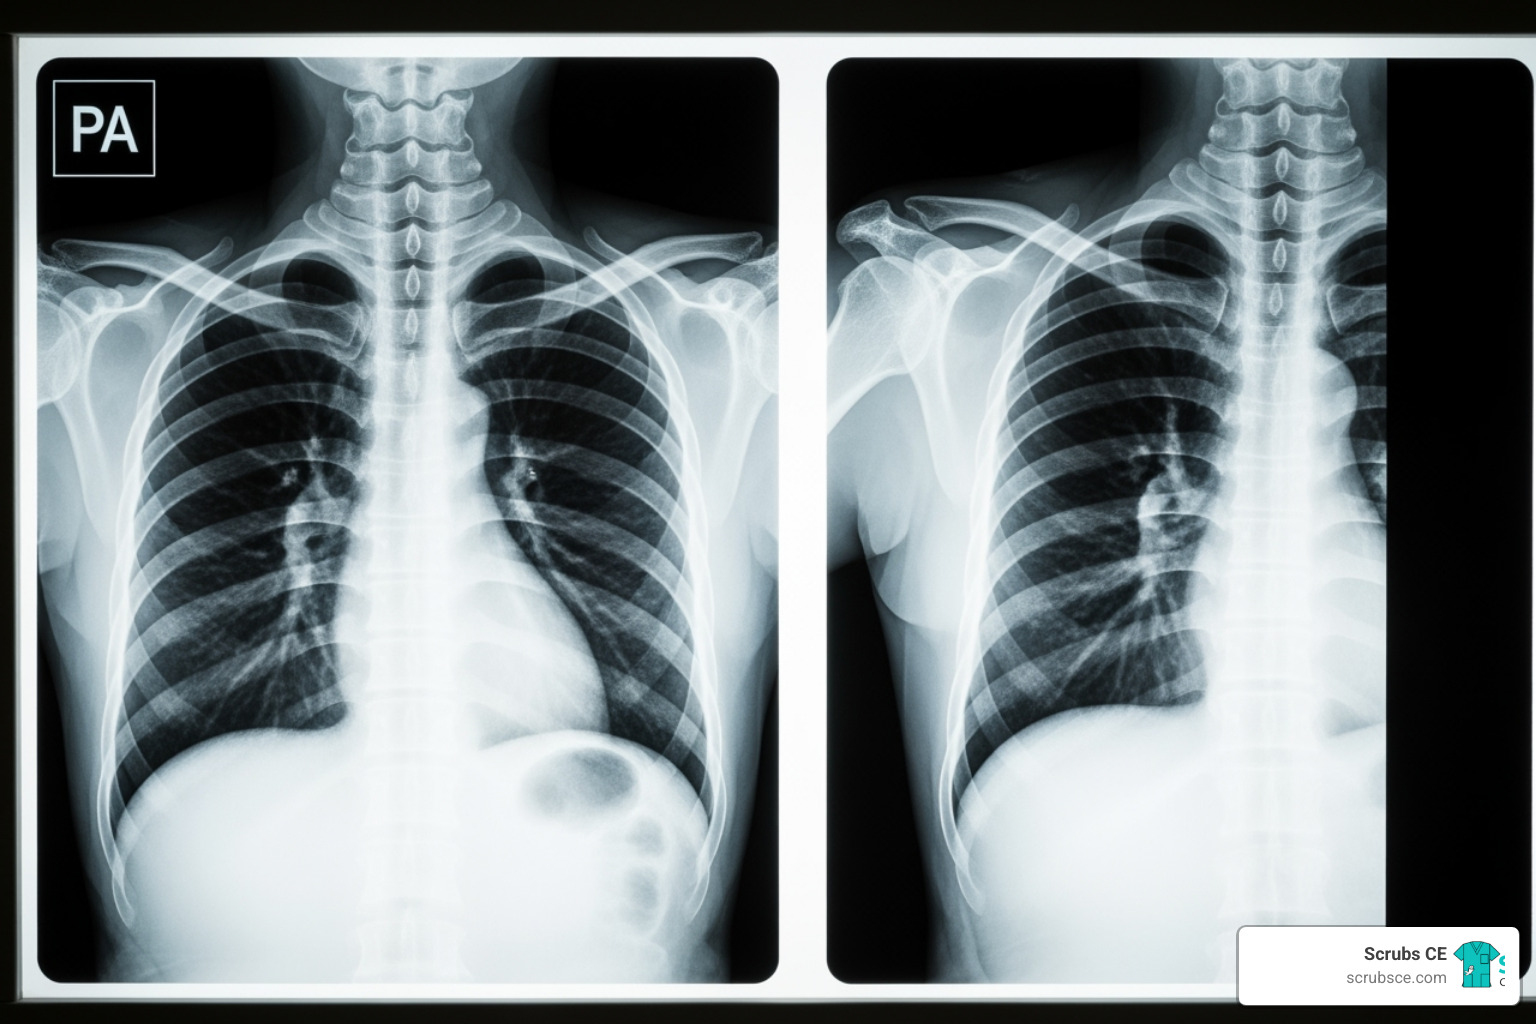

X-ray radiography is the workhorse of imaging. X-ray photons are absorbed differently by various tissues. Dense bone appears white (radiopaque), while air is black (radiolucent), and soft tissues are shades of gray. This differential absorption makes X-rays ideal for quickly identifying fractures, lung issues, and foreign bodies.

The chest X-ray is a frontline tool. Many use the ABCD rule for systematic review: Airways, Breathing (lungs), Cardiac (mediastinum), and Diaphragm. Chest CT offers greater detail, showing individual bronchopulmonary segments, pulmonary vessels, and the mediastinum. The diaphragm appears as a smooth dome separating the chest and abdomen.

- Patient positioning errors, even slight rotation on a chest X-ray, can mimic pathology, such as making a normal heart appear enlarged. Meticulous positioning is crucial for diagnostic accuracy.